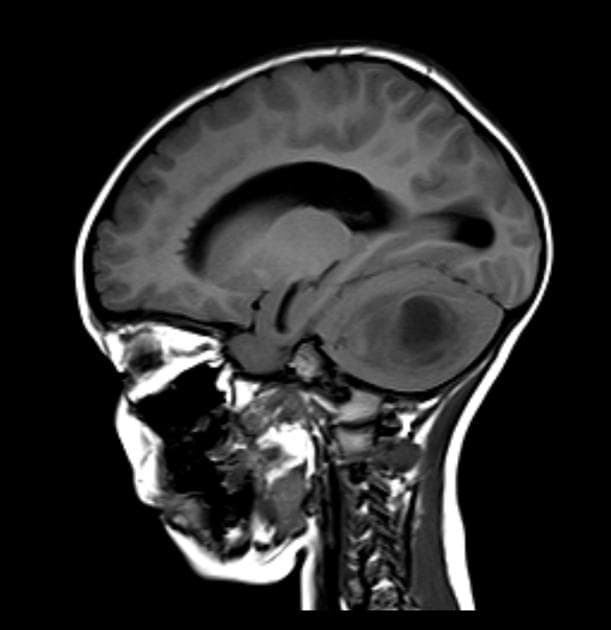

- Có một tổn thương khối nội trục, lớn, ác tính và tăng quang không đồng nhất, xâm lấn cả hai thùy đỉnh và phần vòm của chai thể (corpus callosum).

- Trường hợp này thể hiện hình ảnh điển hình của u nguyên bào thần kinh đệm, IDH dạng hoang dại (glioblastoma, IDH-wildtype) trên cộng hưởng từ tưới máu bằng kỹ thuật ASL (arterial spin labelling).

- Tổn thương đã được sinh thiết và xác nhận là u nguyên bào thần kinh đệm, IDH dạng hoang dại, CNS WHO độ 4 (glioblastoma, IDH-wildtype, CNS WHO Grade 4).

Trường hợp này minh họa các đặc điểm hình ảnh của u nguyên bào thần kinh đệm, IDH dạng hoang dại – một khối u não nguyên phát ác tính cao, thường gặp ở người lớn tuổi. Khối u thường xuất hiện như một tổn thương lớn, tăng quang không đồng đều, có hoại tử trung tâm, bờ không đều và phù mô não lan rộng xung quanh, thường lan qua thân trai (‘u bướm’). Kỹ thuật cộng hưởng từ tưới máu ASL cho thấy tăng tưới máu rõ rệt, phản ánh mức độ tân tạo mạch và hoạt động chuyển hóa cao, tương ứng với ác tính bậc cao. ASL là kỹ thuật đánh giá tưới máu não không cần tiêm chất tương phản, dựa trên việc đánh dấu từ tính nước trong máu động mạch để đo lưu lượng máu não, là lựa chọn an toàn thay thế cho kỹ thuật DSC. Giá trị của ASL trong phân độ u thần kinh đệm và phân biệt với các tổn thương giả như u lympho hay u di căn ngày càng được công nhận trong thực hành lâm sàng.